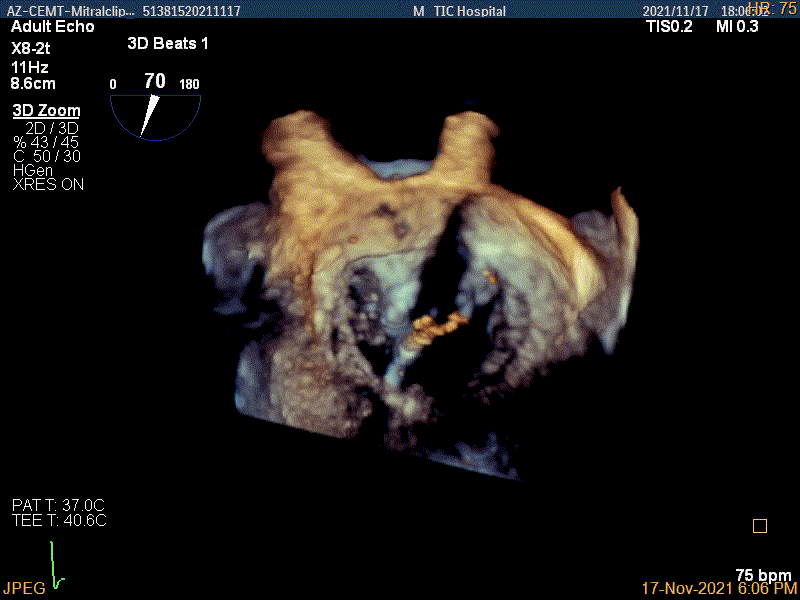

3D视图两个夹子近似并排排列

3D-color视图下两个夹子间少量残余反流